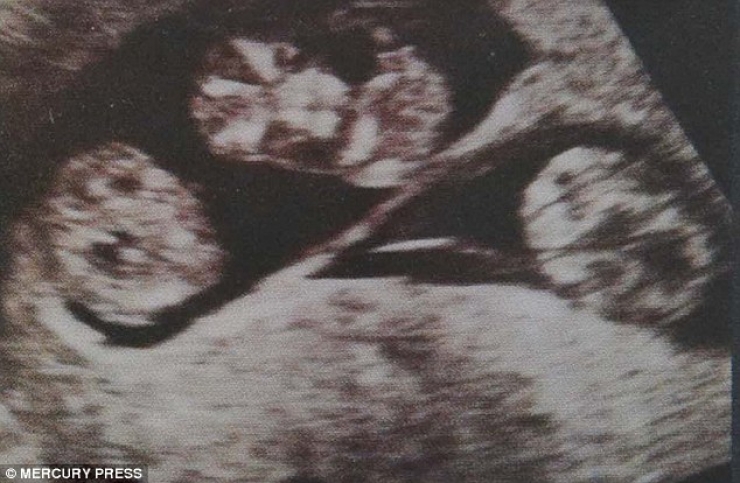

La jeune femme était déjà maman de deux garçons, Drew et Devon, quand on lui a annoncé qu’elle était enceinte de triplés.

Malheureusement, selon l’avis d’un médecin, il y avait de fortes chances pour que l’un des enfants naisse avec le syndrome de Down. On lui a donc conseillé de subir une « réduction sélective » afin de réduire le nombre de foetus pour minimiser les risques de fausses couches ou de problèmes à l’accouchement.

Au final, les 3 bébés sont nés en parfaite santé, à 34 semaines, et en Aout dernier il fêtaient déjà leur premier anniversaire !